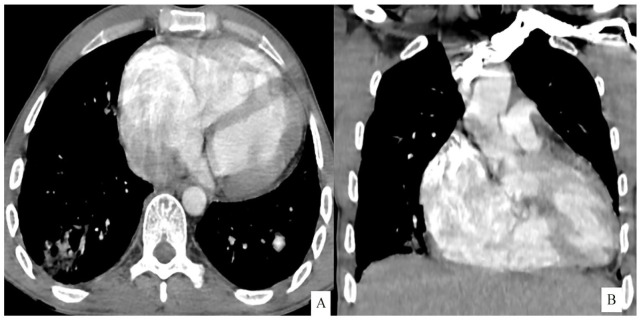

Case presentation: We present the case of a 32 year old male with known history of congenital ventricular septal defect presented to the emergency department with signs of sepsis and dyspnea. Blood cultures were positive for methicillin-sensitive Staphylococcus aureus. An echocardiogram found evidence of endocarditis with multiples intra cavitary vegetations. A CT angiogram demonstrated major right ventricular dilatation, multiple nodules and peripheral opacities, scattered throughout the lungs, indicative of septic emboli. Segmental saccular dilatation of the left lateral basal pulmonary artery consistent with a mycotic aneurysm formation was found. The patient was started on intravenous antibiotics and given the overall satisfactory evolution a conservative approach was pursued. The patient was discharged with antibiotics and scheduled for surgical repair of the ventricular septal defect.